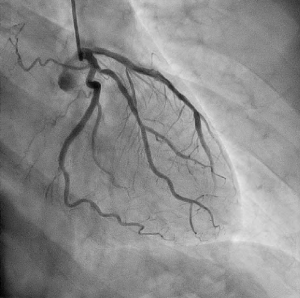

血管撮影検査

腕や足の比較的太い血管からカテーテルと呼ばれる細い管を入れ、心臓や脳、腹部の血管など選択的に挿入し、その先から造影剤を注入し、造影された血管の走行状態、病変まで撮影、治療を行います。

心臓用、頭部用、腹部用(+IVRCT)、ハイブリッド血管撮影装置の4台の装置が稼働しており、緊急検査・治療にも対応しています。